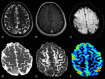

The role of conventional Magnetic Resonance Imaging (MRI) in the detection of cerebral tumors has been well established. However its excellent soft tissue visualization and variety of imaging sequences are in many cases non-specific for the assessment of brain tumor grading. Hence, advanced MRI techniques, like Diffusion-Weighted Imaging (DWI), Diffusion Tensor Imaging (DTI) and Dynamic-Susceptibility Contrast Imaging (DSCI), which are based on different contrast principles, have been used in the clinical routine to improve diagnostic accuracy. The variety of quantitative information derived from these techniques provides significant structural and functional information in a cellular level, highlighting aspects of the underlying brain pathophysiology. The present work, reviews physical principles and recent results obtained using DWI/DTI and DSCI, in tumor characterization and grading of the most common cerebral neoplasms, and discusses how the available MR quantitative data can be utilized through advanced methods of analysis, in order to optimize clinical decision making.